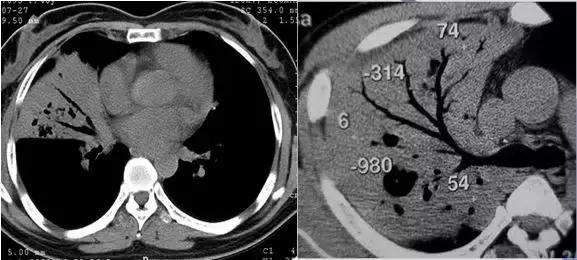

CT征象三:磨玻璃密度影

磨玻璃密度影(GGO):CT表现为肺野低密度背景上略高密度影,边界可清晰也可不清晰,透过其中可显示肺纹理影,有时可见空气支气管征;GGO即可发生在肺间质,也可发生在肺实质病变;预示可能为病变早期。

完全型GGO:恶性占71.4%(其他可能为腺瘤样增生等)

混合型GGO:恶性占93.3%

反映了肺气腔不完全充盈或轻度肺间质的增厚等改变

完全型GGO 混合型GGO

完全型(pGGO)——肺腺癌

完全型(pGGO)——非典型腺瘤样增生

GGO —外伤;GGO—肺间质纤维化